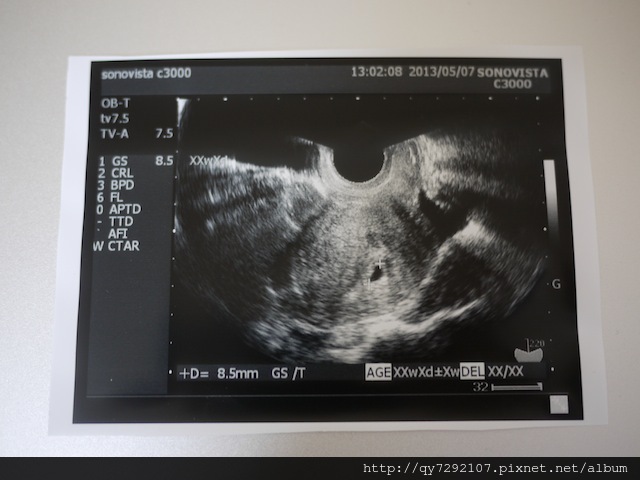

黃金週結束的第一天,我們去做了產檢,出發前的兩天,我以淚洗面,非常難過的渡過黃金週的尾聲,因為兩天前的一個晚上,腰異常的痠,酸的我一整晚無法入睡,隔天一早醒來,又發現肚子忽然變平坦了!我的直覺告訴我Pony沒了,胚胎可能萎縮了,因為去年第一次流產時,腰異常的痠,晚上也無法成眠,然後隔天就出血,自然流產了!第二次流產時,當時已經要11週,肚子很大,當天晚上在姐姐房間吃宵夜時,就覺得肚子忽然消了好多,隔天去醫院檢查,胎兒就沒心跳了。這一次連T先生也納悶肚子怎麼一夜之間變平坦了?!但是今天產檢過後,醫生說無法確定胎兒會不會流產,現在還是懷孕初期,一切都很難講,因為才五週的胚胎,實在看不出來有沒有萎縮,請我下週再複診,若是胚胎沒有長大,萎縮的機率就很高,到時候,他會介紹我們去看不育治療,我跟T先生心裡半喜半憂的回家了。希望一切是我多心,希望我只是一招被蛇咬而嚇怕了,希望Pony可以健康長大,順利生產,成為我們家第二個孩子。